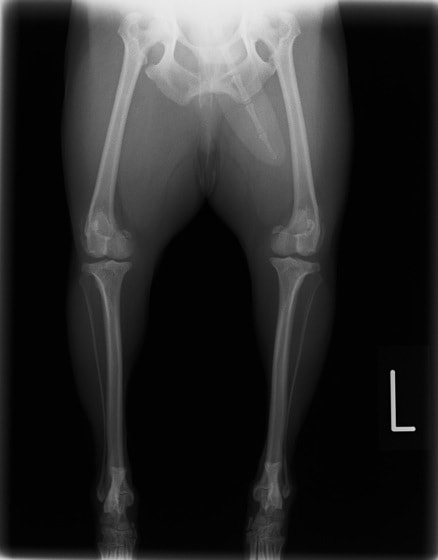

本院では様々な整形外科手術に取り組んでおりますが、膝蓋骨脱臼の症例は、特に多く遭遇する疾患のひとつです。膝蓋骨脱臼は、その進行度に応じて4段階のグレード(グレードI~IV:Iが最も軽度、IVに近づくほど重度)に分類されます。当院ではグレードや症例にあわせて以下の4種類の手術法、

- 1.縫工筋、内側広筋の解放(medial release)

- 2.外側余剰関節包の切除と縫縮術(lateral tightening)

- 3.滑車溝深化術(deepening groove)

- 4.脛骨粗面移植術(tibial tuberosity transposition)

またはantirotational sutureなどを行い、安定した手術成績を残しています。しかし、最終グレードであるIVになり、膝関節の伸展が難しくなったり、骨格の変形が重度になると予後は不良です。状況により、治療のご説明をさせていただきます。